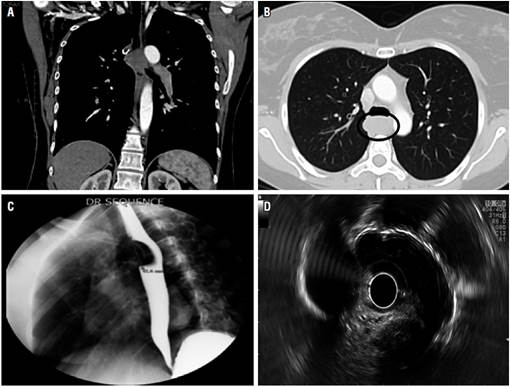

Se trata de una mujer de 41 años de edad que presentó antecedentes de disfagia desde el 2013. Una tomografía de tórax evidenció una lesión esofágica de 4,1 cm (Figuras 1A y 1B), a quien en 2013 intentan realizarle de modo extrainstitucional una resección por toracoscopia; sin embargo, se convierte en toracotomía por tumor de mediastino que compromete la pared del esófago torácico, se toman biopsias compatibles con fascículos de músculo liso sin pleomorfismo nuclear ni mitosis, la necrosis es compatible histopatológicamente con leiomioma benigno del esófago sin realización de inmunohistoquímica. En 2017, por persistencia de la disfagia, se realizaron estudios de extensión: un esofagograma con visualización de una lesión de 4,1 cm que produce alteración del tránsito esofágico (Figura 1C). Se confirma como masa submucosa por ultrasonografía endoscópica (Figura 1D) de aproximadamente 3,6 cm en su eje mayor a lo largo de la pared anterior del esófago en el tórax superior, inferior a la vena ácigos, apareciendo como masa hipo vascular sin adenopatías paraesofágicas. La resección del tumor se consideró necesaria debido al tamaño de la lesión.